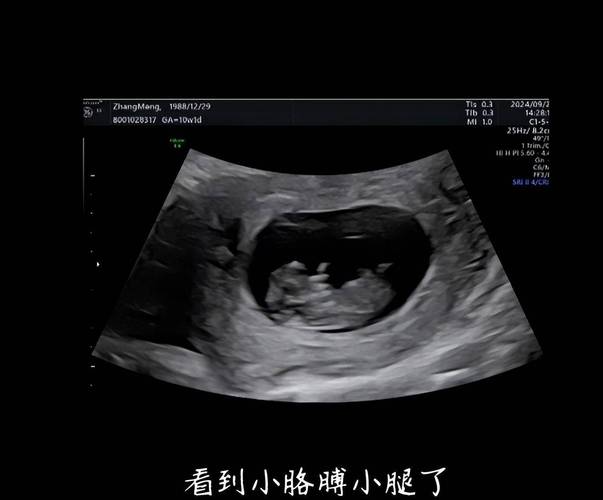

在孕50天左右,B超下看到的“蝌蚪”形状,通常是指胚胎和卵黄囊的组合影像。

- “蝌蚪”的头部:这是正在发育的胚胎,在孕50天,胚胎大约有1-1.5厘米长,像一个微小的“C”字形,因为它的背部已经开始变直,但还没有完全伸直,这个“C”形的头部就是胚胎的身体。

- 卵黄囊:在胚胎旁边,您会看到一个圆形或椭圆形的无回声区,这就是卵黄囊,它的作用就像一个临时的“营养仓库”,为早期发育的胚胎提供重要的营养,直到胎盘功能完全建立,它看起来就像是连接在胚胎上的一个“小圆球”或“小尾巴”。

- 孕囊:整个“蝌蚪”结构都位于一个更大的、充满液体的圆形结构内,这就是孕囊,孕囊是胚胎着床后形成的“小房子”,保护着胚胎。

当B超影像把这些结构组合在一起时,就非常像一个可爱的小“蝌蚪”了。这是早期孕囊、胚胎和卵黄囊的经典B超表现,是生命正在健康孕育的标志!